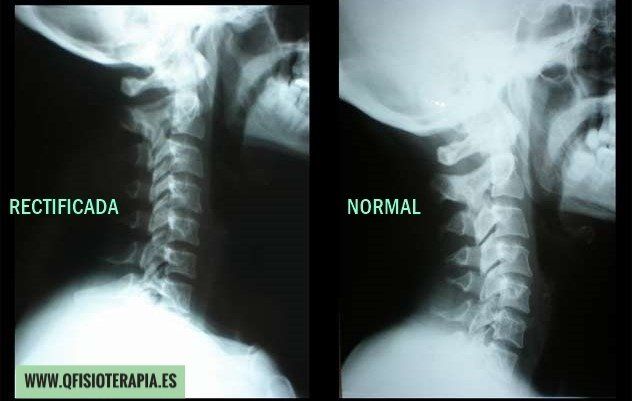

Empecemos explicando qué es una rectificación cervical. Las vertebras cervicales poseen una curvatura fisiológica natural que se denomina lordosis cervical. Gracias a esta curvatura, el cuello puede resistir grandes cargas de compresión y minimizar el estrés de las vertebras.